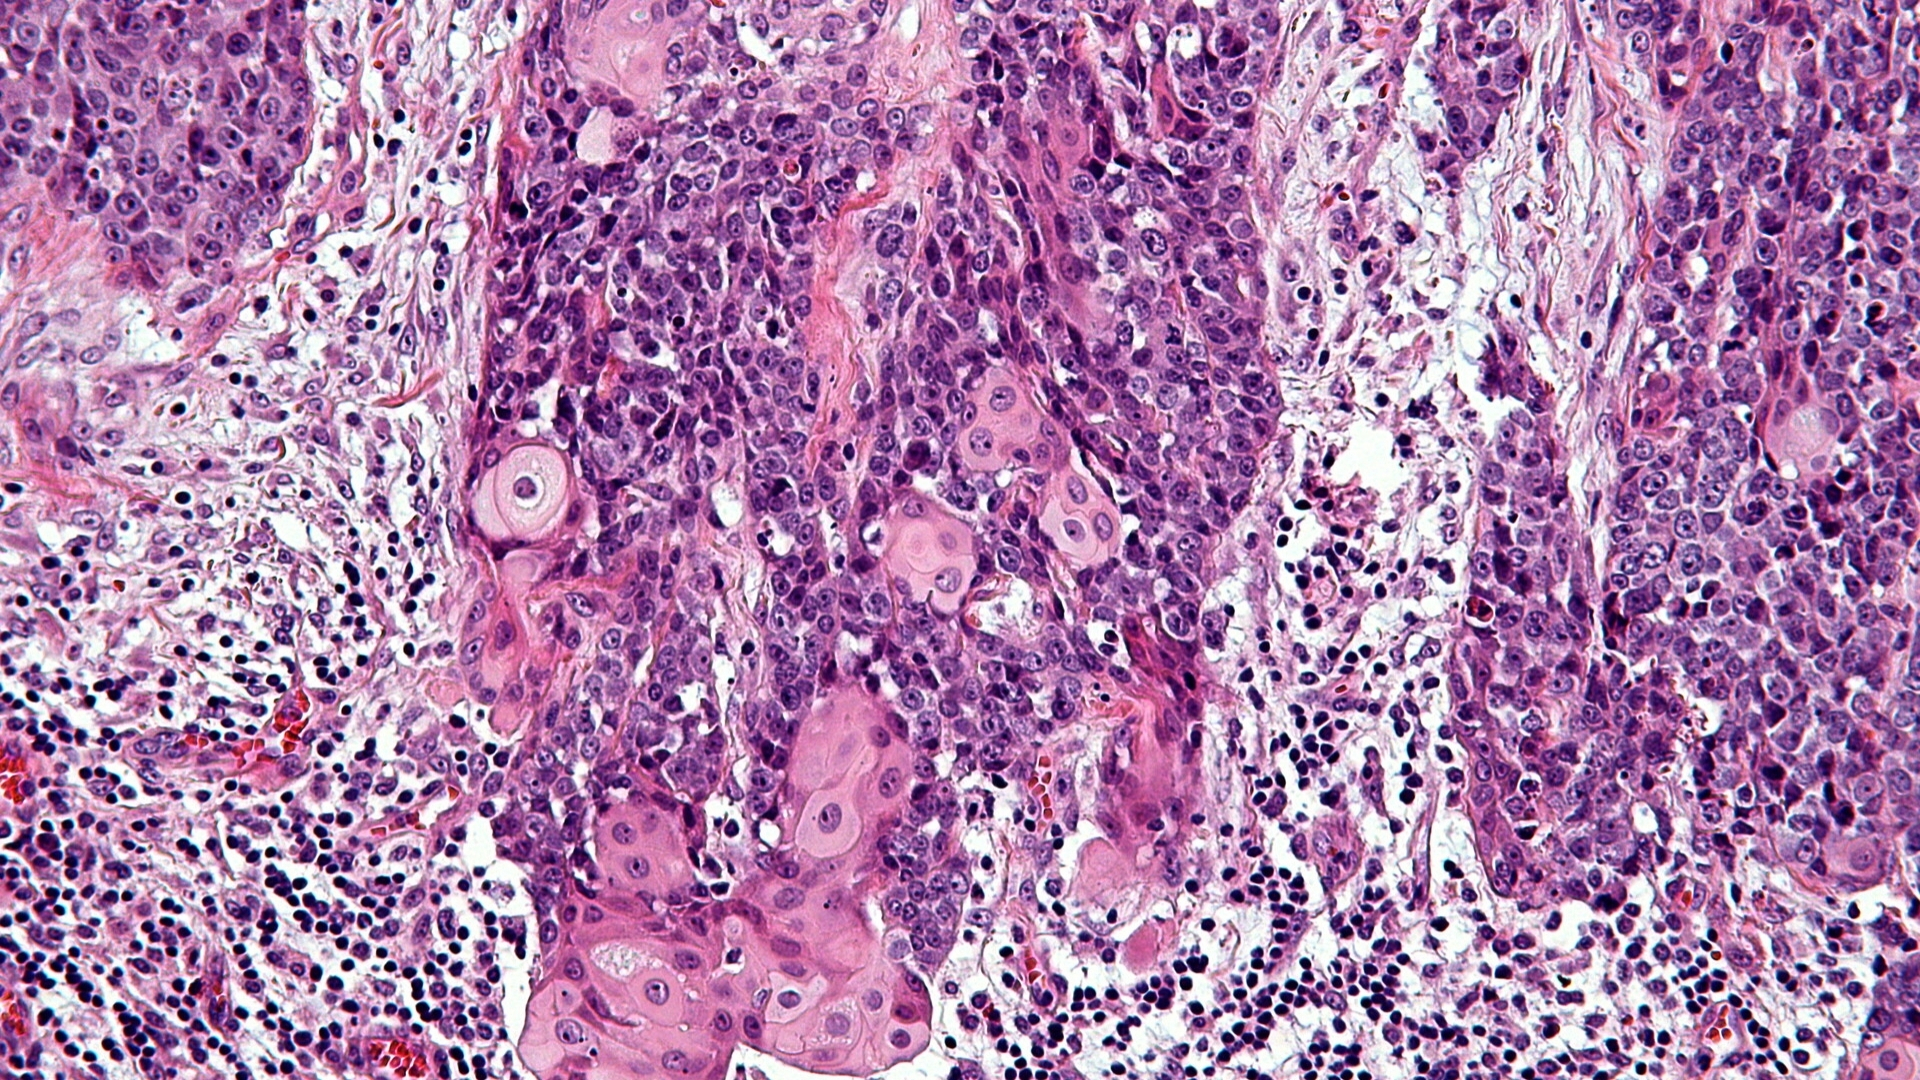

中線管癌 (NUT 癌症)是一種極為罕見但具侵略性的癌症,特徵為特定的基因突變。這種惡性腫瘤通常發生在身體的中線結構,如肺、縱膈、鼻腔或唾液腺,其特徵是位於 15 號染色體的睪丸核蛋白 (NUTM1) 基因重排。由此產生的基因改變會促進異常的細胞增殖和快速的腫瘤生長。

近年來,由 James P. Allison 教授和 Gregg Semenza 博士等知名諾貝爾獎得主所贊同的突破性研究,已闡明 NUT Carcinoma 的分子結構。這種癌症的表現主要是由於融合的染色體易位所致。 NUTM1 基因與 BRD4 或 BRD3 等基因,造成快速且無法控制的細胞分裂。

• 以涉及 NUT 基因的基因易位為標記。

中線縱膈癌 (Midline Tract Carcinoma) 主要是由涉及 NUTM1 基因的特定基因易位所引起。與 BRCA1/BRCA2 基因突變相關的乳癌或 EGFR 基因突變相關的肺癌不同,NUT Carcinoma 特別涉及融合基因異常 (尤其是 NUT-BRD4)。雖然大多數患者不會遺傳這些突變,但已觀察到罕見的家族聚集,顯示個別病例有遺傳傾向。